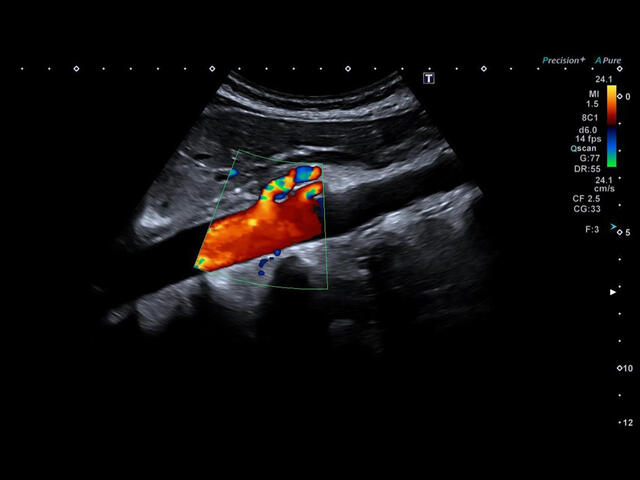

- расширенный динамический поток (ADF),

Aplio a550 может работать с линейным матричным датчиком и поддерживает новейшие монокристаллические датчики. Также Aplio a550 поддерживает большое количество дополнительных опций, таких как - SMI, Компрессионная эластография, Эластография сдвижной волны, Smart Fusion, исследования с использованием контраста (CEUS), 3D реконструкции в реальном времени (4D), функции автоматической оценки подвижности миокарда и фракции выброса.

- SMI. Опция, упрощающая визуализацию микроциркуляторного русла. С ее помощью обследуются сосуды с низкой интенсивностью кровотока, изучаются наиболее тонкие структуры. SMI упрощает диагностику новообразований, минимизирует вероятность ошибки.

CDI-Режим - Цветной допплер

DP-Режим - Энергетический доплер

Dir.PD-Режим - Направленный энергетический доплер

Уровень сосудистой визуализации SMI в сочетании с высокой частотой кадров повышает диагностическую достоверность при оценке поражений, кист и опухолей.

SMI с цветовой кодировкой позволяет одновременно отображать информацию о потоках и оттенках серого с высокой временной и пространственной информацией.